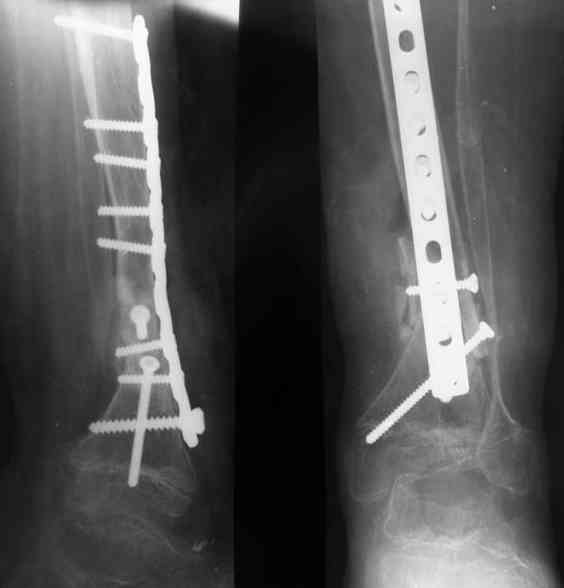

Уважаемые коллеги! В отделении на лечении наблюдается пациент 16 лет с диагнозом: Псевдоартроз костей левой голенив нижней трети. Вальгусная деформация обоих коленных суставов. Укорочение левой н/конечности11см. С 1997 года состоит на учёте у онколога с диагнозом: Рабдомиосаркома мышц тазового дна IV ст., с метастазами в метафизы берцовых костей.Проведена полихимиотерапия, лучевая терапия. В 1998 г. удаление опухоли. Послеоперационный период без особенностей. С 1998 года со стороны онкологии ремиссия, перестройка очагов метастазирования в берцовых костях по типу фиброзной дисплазии.В 1999 г. патологический перелом костей левой голени в н/трети. Лечение в гипсе 1.5 месяца, затем компрессионно-дистракционный остеосинтез апп. Илизарова. Сращения на месте псевдоартроза не достигнуто. С 1999г. ходит без нагрузки на левую н/конечность. Выраженный остеопороз костей н/конечностей. 17.11.05. Операция: Костная пластика зоны псевдоартроза левой б/берцовой кости по типу "русский замок", остеосинтез пластинкой и винтами. После начала нагрузки на конечность рецидив деформации, миграция фиксаторов. 05.12.06. Операция: Удаление фиксаторов из левой голени. Шарнирная остеотомия трети левой б/берцовой кости, остеотомия м/берцовой кости. Дистракционный остеосинтез апп. Илизарова. Устранены основные виды деформации б/берцовой кости. Планировали в дальнейшем несвободную костную аутопластику и интрамедуллярный остеосинтез с блокированием, но кость очень тонкая, склерозированная, выраженный остеопороз. Возникают большие сомнения о возможности сращения даже при этих условиях. Будем рады услышать ваши мнения по дальнейшему лечению данного пациента. Екатериан Анатольевна Озерова, детское отделение УНИИТО

Заранее прошу прощения у неизвестных коллег, но кому пришло в голову синтезировать такую проблемную голень LC DCP по гребню большеберцовой кости? С какой целью выполнена остеотомия? С уважением, Ильин В.С.